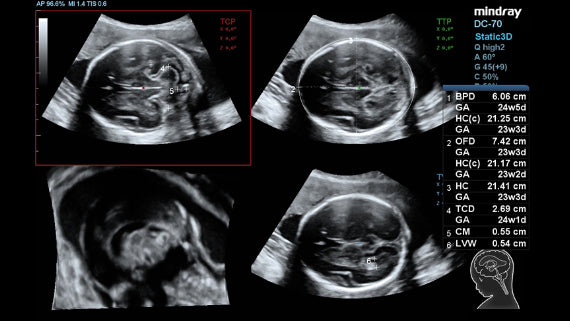

El Ultrasonido premiumDC-70 X-Insight de Mindray es un equipo de última tecnología para ecografías. Ofrece excelente resolución y sensibilidad para una visualización clara y precisa de los tejidos bajo examen. Esta máquina de alto rendimiento ofrece eficiencia y fiabilidad para una mayor precisión diagnóstica.